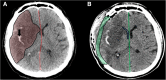

Malignant stroke occurs in a subgroup of patients suffering from ischemic cerebral infarction and is characterized by neurological deterioration due to progressive edema, raised intracranial pressure, and cerebral herniation. Decompressive craniectomy (DC) is a surgical technique aiming to open the "closed box" represented by the non-expandable skull in cases of refractory intracranial hypertension. It is a valuable modality in the armamentarium to treat patients with malignant stroke: the life-saving effect has been proven for both supratentorial and infratentorial DC in virtually all age groups. This leaves physicians with the difficult task to decide who will require early or preemptive surgery and who might benefit from postponing surgery until clear evidence of deterioration evolves. Together with the patient's relatives, physicians also have to ascertain whether the patient will have acceptable disability and quality of life in his or her presumed perception, based on preoperative predictions. This complex decision-making process can only be managed with interdisciplinary efforts and should be supported by continued research in the age of personalized medicine.